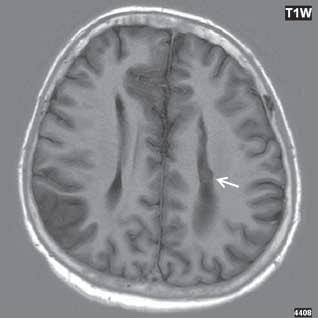

I.1.6 Schizencefalie

Mozková malformace („rozštěp mozku“), která je charakterizována komunikací mezi povrchem mozku a komorovým systémem, kortex v okolí schizencefalie bývá polymikrogyrický. Měkké pleny mozkové z povrchu mozku přecházejí do vytvořeného rozštěpu a komunikují s ependymem v komorovém systému. Šedá hmota lemující schizencefalii bývá zesílena a ztrácí normální architekturu. Obvykle zasahuje do oblasti insuly. Rozlišujeme dvě formy schizencefalie: zavřenou „closed lip“ a otevřenou „open lip“. Příčinou je porucha migrace. Až u poloviny případů je oboustranná. V 70 % je absence septum pellucidum.

Zobrazení

CT zobrazí komunikaci vyplněnou likvorem mezi mozkovou komorou a povrchem mozku.

Modalita MR je optimální vyšetřovací metoda pro zobrazení schizencefalie, i když rozsáhlé defekty mohou být diagnostikovány již prenatálně pomocí UZ. Zobrazíme rozštěp, komunikaci, mezi povrchem mozkové tkáně a mozkovými komorami. U open lip je patrný široký kanál, v T2W obrazu vyplněný hypersignálním likvorem, po stranách lemovaných dysplastickou šedou hmotou – je nižšího signálu. V okolí vyústění schizencefalie na povrch mozku lze často pozorovat kortikální dysplazii (polymikrogyrii, abnormální gyry), šedá hmota lemující schizencefalii bývá zesílená, tvoří nepravidelné gyry, není přesné ohraničení mezi šedou a bílou hmotou, v okolí je častá nodulární heterotopie. Uzavřený typ je někdy málo nápadný, je patrný

„pruh šedé hmoty“ vedoucí k postranní komoře, dysplastická šedá hmota může mít tvar dlažebních kostek. Často je přítomna hypotrofie optické dráhy, hypofýzy, corpus callosum…

(closed lip), rozštěp mozku lemuje šedá hmota mozková; stejný pacient jako na obr I 1 6a

Obr. I.1.6c Schizencefalie (closed lip) (šipka)

Obr. I.1.6d Schizencefalie (closed lip), rozštěp mozku lemuje šedá hmota mozková, vlevo subependymální heterotopie (šipka) e f